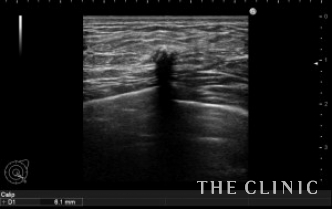

しこりの位置と、エコー所見です。

左は11.8mm と6.1mm

乳輪切開で摘出しましたが、左の6.1mmの石灰化は非常に小さく摘出に苦労しました。